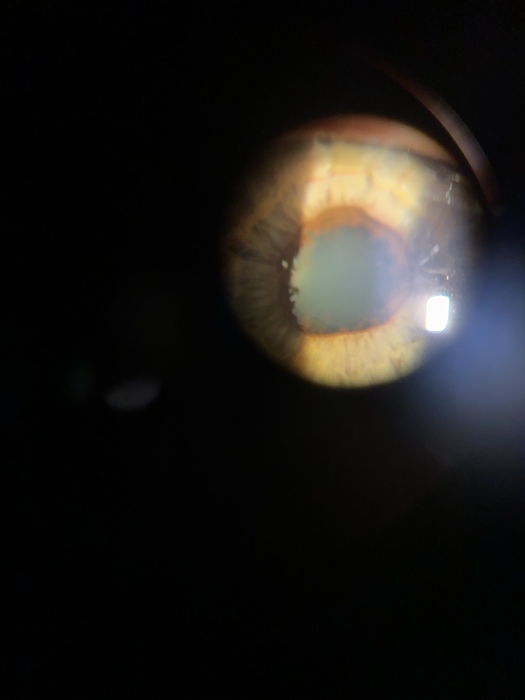

pokaloka2,

Пример переднего увеита (иридоциклит). Велся у меня пациент. На фото, гониосинехии (радужка из за воспаления спаялась с хрусталиком). Преципитаты (отложения клеток на зданей поверхности роговицы).